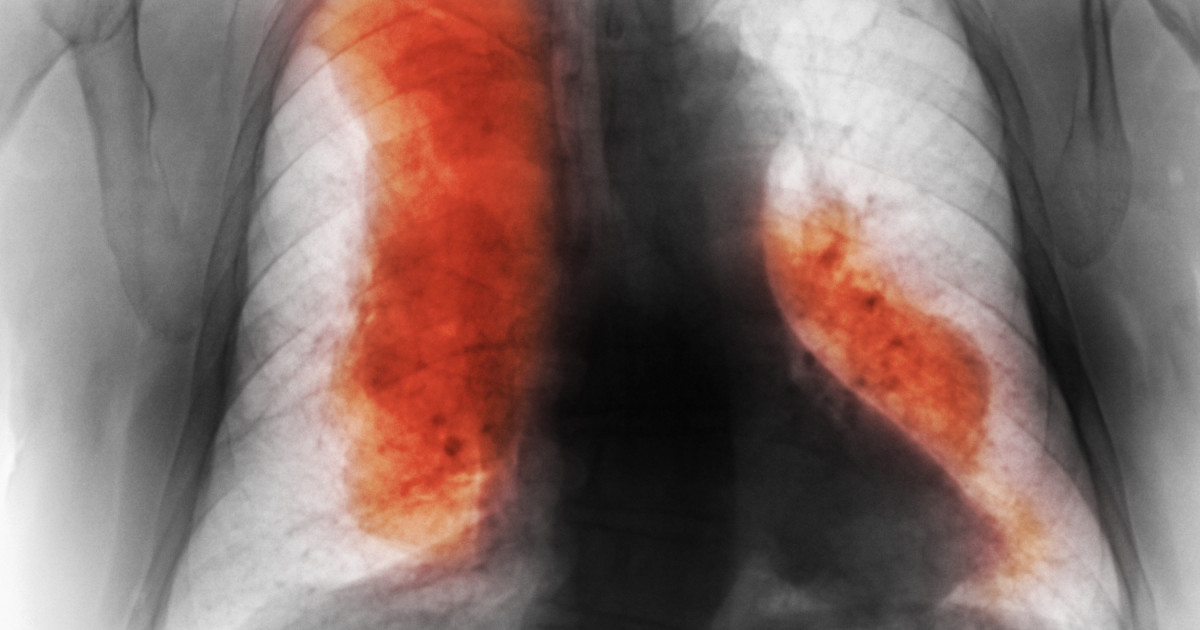

Creșterea alarmantă a deceselor cauzate de cancer

Un studiu recent publicat în jurnalul științific The Lancet a adus în atenție o problemă de sănătate publică extrem de gravă: numărul deceselor cauzate de cancer ar putea depăși 18,5 milioane până în 2050. Această estimare, care se bazează pe datele din 204 de țări și teritorii, subliniază o tendință îngrijorătoare care necesită acțiuni imediate și eficiente.

Deși s-au înregistrat progrese semnificative în tratamentele pentru cancer, numărul cazurilor noi a crescut de peste două ori din 1990, atingând 18,5 milioane în 2023. Această situație sugerează o necorelare între progresele în tratament și creșterea alarmantă a incidenței bolii. În plus, numărul deceselor a crescut cu 74%, ajungând la 10,4 milioane, ceea ce ridică semne de întrebare asupra eficienței actualelor strategii de prevenire și tratament.

Studiul subliniază că, fără acțiuni și finanțare adecvată, numărul de cazuri noi de cancer ar putea crește cu 61% în următorii 25 de ani, atingând 30,5 milioane în 2050. De asemenea, numărul anual de decese ar putea crește cu aproape 75%, ajungând la 18,5 milioane. Această previziune sumbră evidențiază urgentitatea de a reevalua strategiile actuale și de a aloca resurse suplimentare pentru combaterea acestei boli devastatoare.